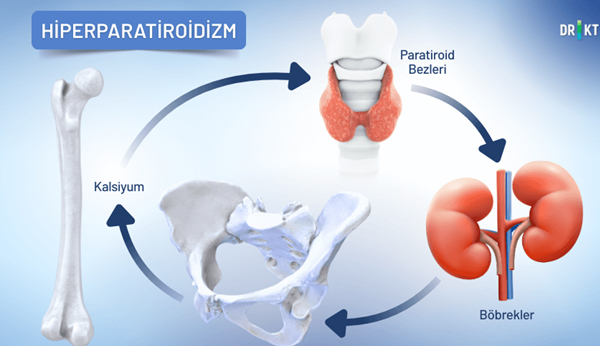

هیپرپاراتیروئیدیسم

هیپرپاراتیروئیدیسم زمانی رخ میدهد که غدد پاراتیروئید، که در گردن قرار دارند و مسئول تنظیم تعادل کلسیم بدن هستند، بیش از حد فعال شوند و هورمون پاراتیروئید (PTH) بیشتری ترشح کنند. عملکرد اصلی این هورمون انتقال کلسیم از استخوانها به خون در هنگام کاهش سطح کلسیم خون است. با این حال، در صورت وجود هیپرپاراتیروئیدیسم، این فرآیند از کنترل خارج میشود و استخوانها به طور مداوم کلسیم از دست میدهند.

در نتیجه، استخوانها تراکم خود را از دست میدهند، ضعیف و شکننده میشوند. هیپرپاراتیروئیدیسم اغلب در اثر تومور خوشخیم یا بزرگ شدن غدد پاراتیروئید ایجاد میشود و علت درد استخوان، ضعف و خستگی است.